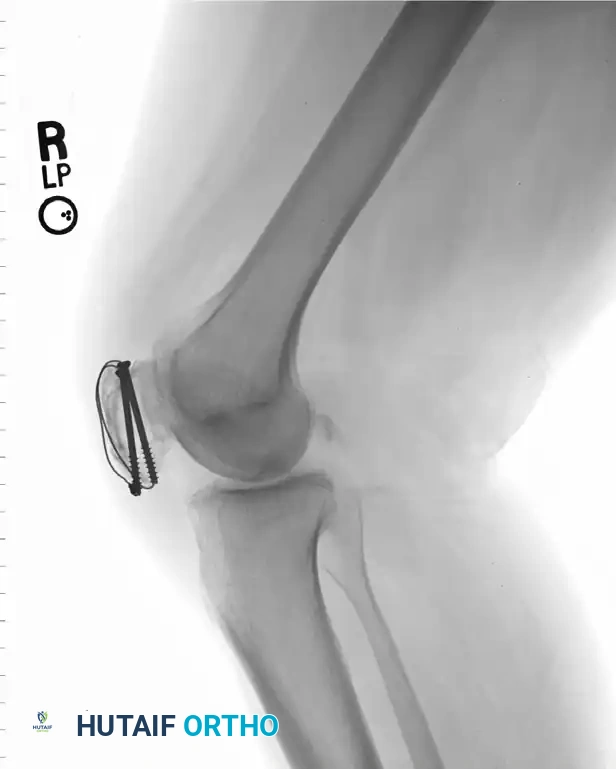

SURGICAL TECHNIQUE 54-21: STANDARD TENSION BAND WIRING

The following represents the definitive, step-by-step execution of the AO tension band wiring technique using Kirschner wires (K-wires).

3. Kirschner Wire Insertion

With the fracture anatomically reduced and held firmly with clamps, drill two 2.0-mm K-wires from inferior to superior through each fragment.

* Place these wires approximately 5 mm deep to the anterior surface of the patella.

* Position them along lines dividing the patella into medial, central, and lateral thirds.

* It is imperative to insert the wires as parallel as possible to facilitate uniform compression and prevent binding.

4. Application of the Tension Band Wire

Pass a strand of 18-gauge stainless steel wire transversely through the quadriceps tendon attachment, as close to the superior bone pole as possible, passing deep to the protruding K-wires.

Route the wire over the anterior surface of the reduced patella. Pass it transversely through the patellar tendon attachment on the inferior fragment, again keeping it deep to the protruding K-wires and as close to the bone as possible. Bring the wire back over the anterior patellar surface to meet the upper end.

While a simple loop can be used, placing the wire in a figure-of-eight fashion is biomechanically superior, as it provides better rotational stability and more uniform compression across the fracture site.

5. Tensioning and Verification

Tighten the 18-gauge wire symmetrically. The wire should be tightened until the fracture is slightly overcorrected (opened microscopically on the anterior surface), ensuring maximum compression at the articular surface.

6. Securing the Hardware

Once compression is confirmed, the K-wires must be secured to prevent postoperative migration—a common complication.

* Bend the upper ends of the two K-wires acutely anteriorly (approximately 180 degrees).

* Cut the bent ends short.

* Using a heavy impactor and mallet, embed the bent ends deep into the superior margin of the patella, ensuring they sit posterior to the wire loops. This locks the tension band in place.

* Cut the protruding ends of the K-wires short inferiorly, leaving just enough length to prevent the wire loop from slipping off, but short enough to avoid irritating the patellar tendon.